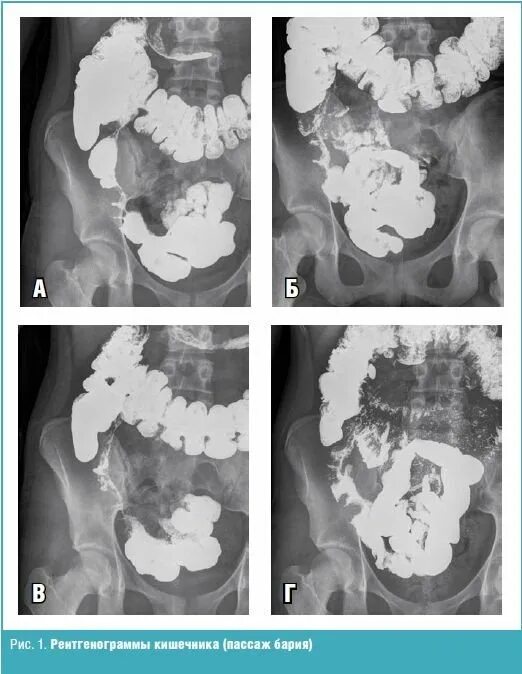

Пассаж кишечника